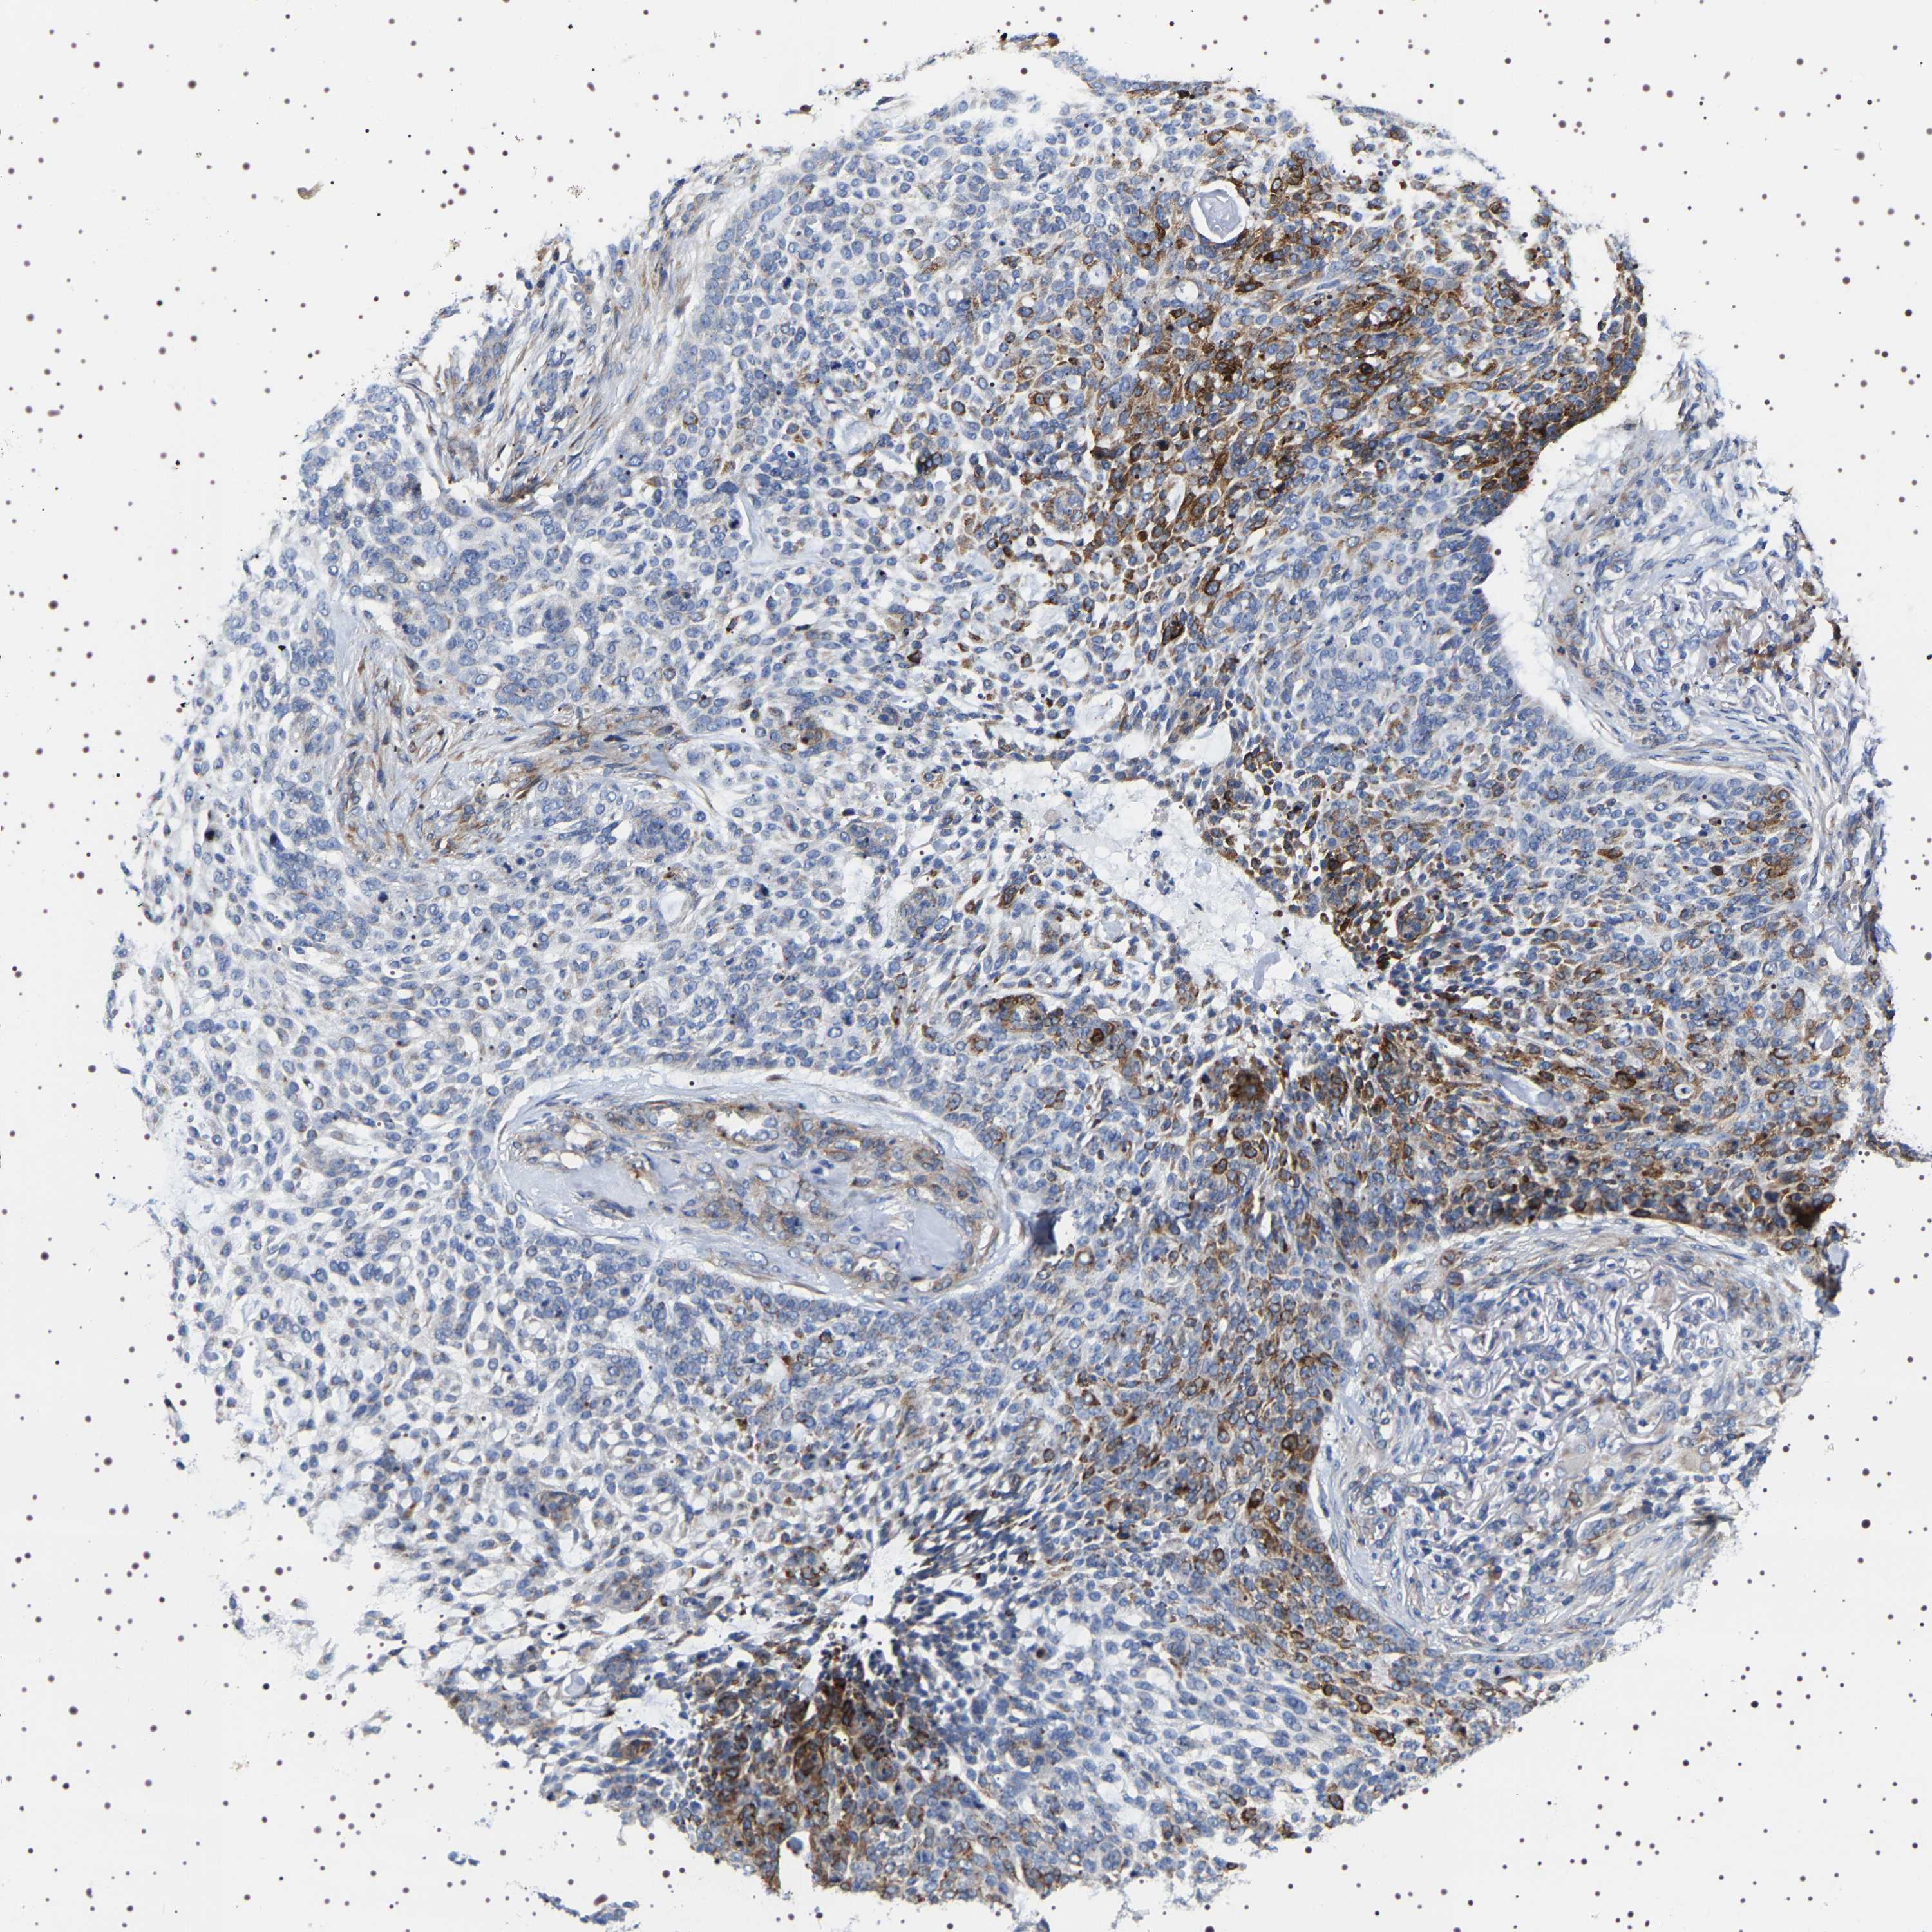

SKIN CANCER - Protein expressioni

A mouse-over function shows sample information and annotation data. Click on an image to view it in a full screen mode. Samples can be filtered based on level of antibody staining by selecting one or several of the following categories: high, medium, low and not detected. The assay and annotation is described here.

Antibody stainingi

Antibody staining in the annotated cell types in the current human tissue is reported as not detected, low, medium, or high, based on conventional immunohistochemistry profiling in selected tissues. This score is based on the combination of the staining intensity and fraction of stained cells.

Each image is clickable and will lead to virtual microscopy that enables deeper exploration of all samples and also displays staining intensity scores, fraction scores and subcellular localization as well as patient and tissue information for each sample.

Antibody HPA018038

Antibody HPA020762

Staining

High

Medium

Low

Not detected

Intensity

Strong

Moderate

Weak

Negative

Quantity

>75%

75%-25%

<25%

None

Location

Nuclear

Cytoplasmic/membranous

Cytoplasmic/membranous,nuclear

Squamous cell carcinoma in situ, NOS

Squamous cell carcinoma, NOS

Squamous cell carcinoma, metastatic, NOS

Basal cell carcinoma